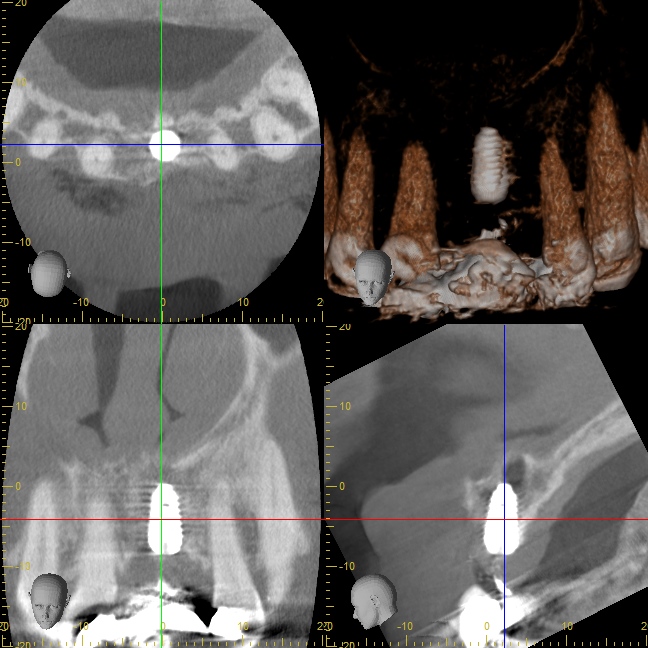

インプラントを埋め込む部分の歯茎が痩せてしまっていることが分かります。

インプラントの外側に骨が足りないことが分かります。

内側に既存の骨、外側に追加した人工骨があります。

この状態で3ヶ月ほどおくことで、インプラントは安定します。